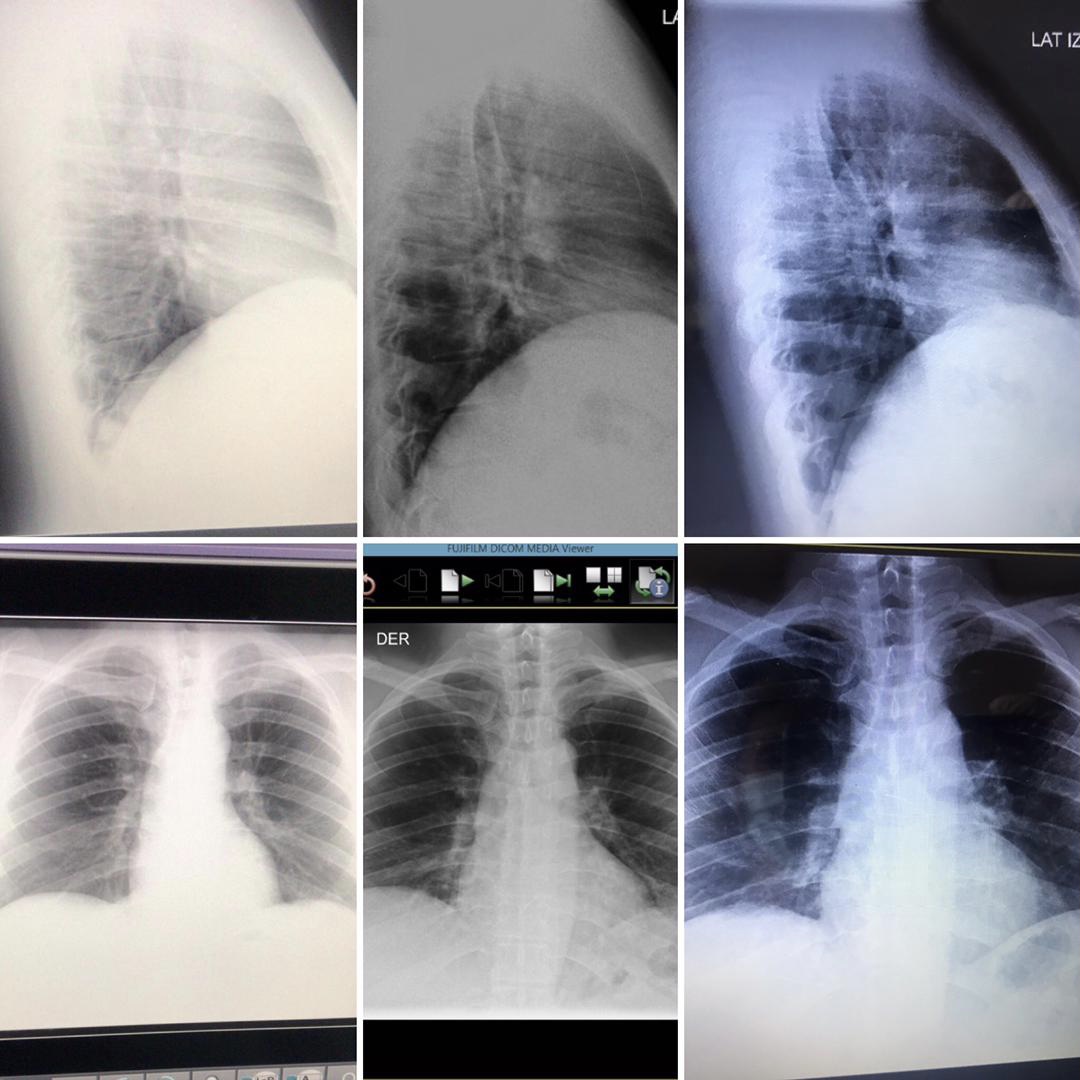

Empiezo el día sintiéndome muy cansado, con síntomas de fiebre, malestar leve y dudando si sería una gripe por mojarme días anteriores o covid, decido ponerme doble tapabocas irme a trabajar con distancia entre las personas!. Pasando las horas decido irme a mi casa porque los síntomas eran mayores, pero antes paso por una clínica para hacerme un rayos X de tórax, para mi sorpresa este fue el resultado:

El daño ya estaba hecho. Decido tratarme en casa por los síntomas que me dieran solo con acetaminofen, grave error.

Me Levantaron para ir a la consulta con el médico neumonologo y como pude fui con mis rayos X, llegamos a la consulta, esperamos una hora sentados en las escaleras para no estar cerca de personas, cuando toco mi turno, el doctor toma mi saturación estaba en 92, tenia tos, el corazón acelerado ( y vaya que no les he contado… soy hipertenso algo grave en esta enfermedad ) y el malestar cada vez peor, el doctor me manda acetaminofen, un anticoagulante en pastillas, dexametazona intectado por 10’dias intramuscular y ya!. A la casa muy normal, me quede inconforme con esto pero la verdad no tenía fuerzas de nada, iba en el carro desmayado de lo mal que me sentía.

Ya mi cuerpo me decía que tenía que hacer algo porque cada día empeoraba, cuando ya decía que no podía ser peor, era mucho peor, decidimos Volver al Médico que me Mando antes de llegar a realizarme unos exámenes de sangre y una resonancia de tórax, llegamos con los estudios y nuevamente los reviso me mando A la casa hasta que le pregunté y no voy a tomar antibióticos?. En ese Momento me dijo que sí que los tomara ( si no él preguntaba no me los mandaba ) ya me di cuenta que el señor no trataba con pacientes covid y que a pesar de ser muy bueno es una enfermedad que necesita ser tratada para Poder “entenderla” muchos estudios y aún no se sabe ni el 20% de ella, por eso puedo entender al doctor hasta cierto punto.

Me repititen los exámenes el día viernes 14 de abril donde por muy poco estaba mejorando la doctora insistía en que tenía que estar hospitalizado, pero mi fuerza de voluntad y deseo de vivir eran mayores!.

Los exámenes empezaron a mejorar mucho!. La doctora se sorprendió al verme sin el oxígeno puesto y se alegró!. Todos bajos la guardia, lo peor había pasado!. Tuve 15 días de reposo absoluto después de esto!. Ya tengo una semana y 4 días que estoy volviendo a lo rutina, cuidándome el doble, pensando en lo afortunado que soy en estar vivo, agradeciéndole a dios por permitirme estar aquí!.

De izquierda a derecha mi mejoría